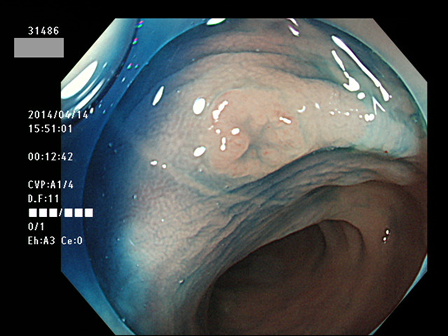

上記100名より抽出した平坦・陥凹型腺腫(=癌化の危険が高いが見落としやすい病変)の内視鏡写真